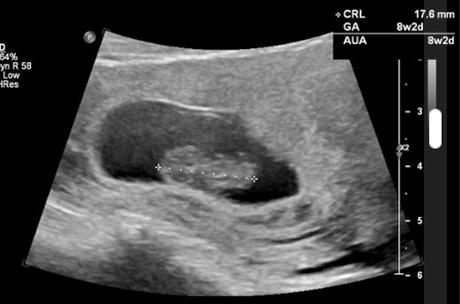

Ultrasound picture of 8 week old embryo

The ultrasound images below show the difference in the first trimester and the second trimester.

The image below shows how an ultrasound is used to monitor a baby’s development and look for abnormalities.

First trimester ultrasound Second trimester ultrasound